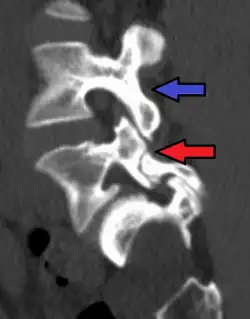

Anterolisthesis L5/S1 -

Anterolisthesis L5/S1. Blue arrow normal pars interarticularis. Red arrow is a break in pars interarticularis. -

Anterolisthesis L5/S1

Computed tomography (CT)

Computed tomography can be helpful in evaluating bony vertebral abnormalities, such as fractures.[38] This can be helpful in determining if the fracture is a new, old, and/or progressing fracture.[38] CT use in spondylolisthesis evaluation is controversial due to high radiation exposure.[39]